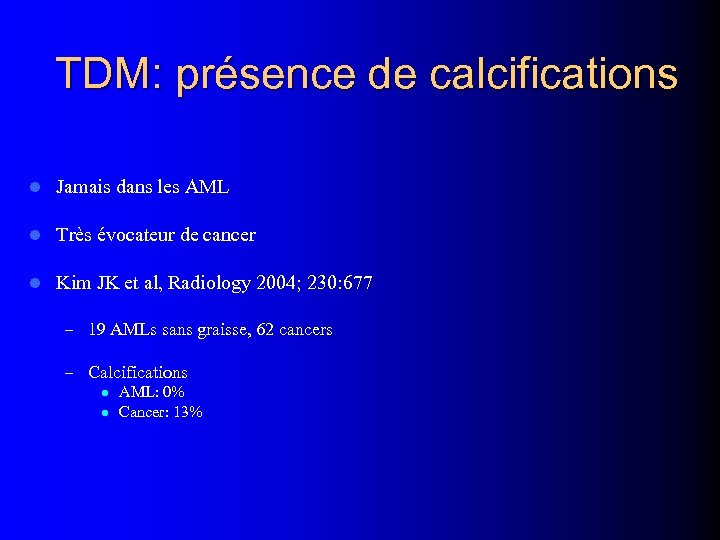

TDM: présence de calcifications l Jamais dans les AML l Très évocateur de cancer l Kim JK et al, Radiology 2004; 230: 677 – 19 AMLs sans graisse, 62 cancers – Calcifications l AML: 0% l Cancer: 13%

TDM: présence de calcifications l Jamais dans les AML l Très évocateur de cancer l Kim JK et al, Radiology 2004; 230: 677 – 19 AMLs sans graisse, 62 cancers – Calcifications l AML: 0% l Cancer: 13%